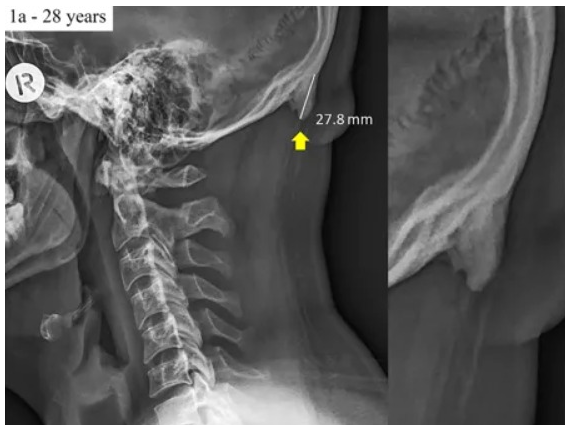

특히 스마트폰을 주로 사용하는 젊은층은 중장년층에 비해 이 부분이 훨씬 더 많이 튀어나온 것으로 확인됐다. 한 예로 연구 대상자인 28세의 한 젊은이의 융기는 2.78㎝인데 반해 58세의 한 중장년은 2.45㎝였다.